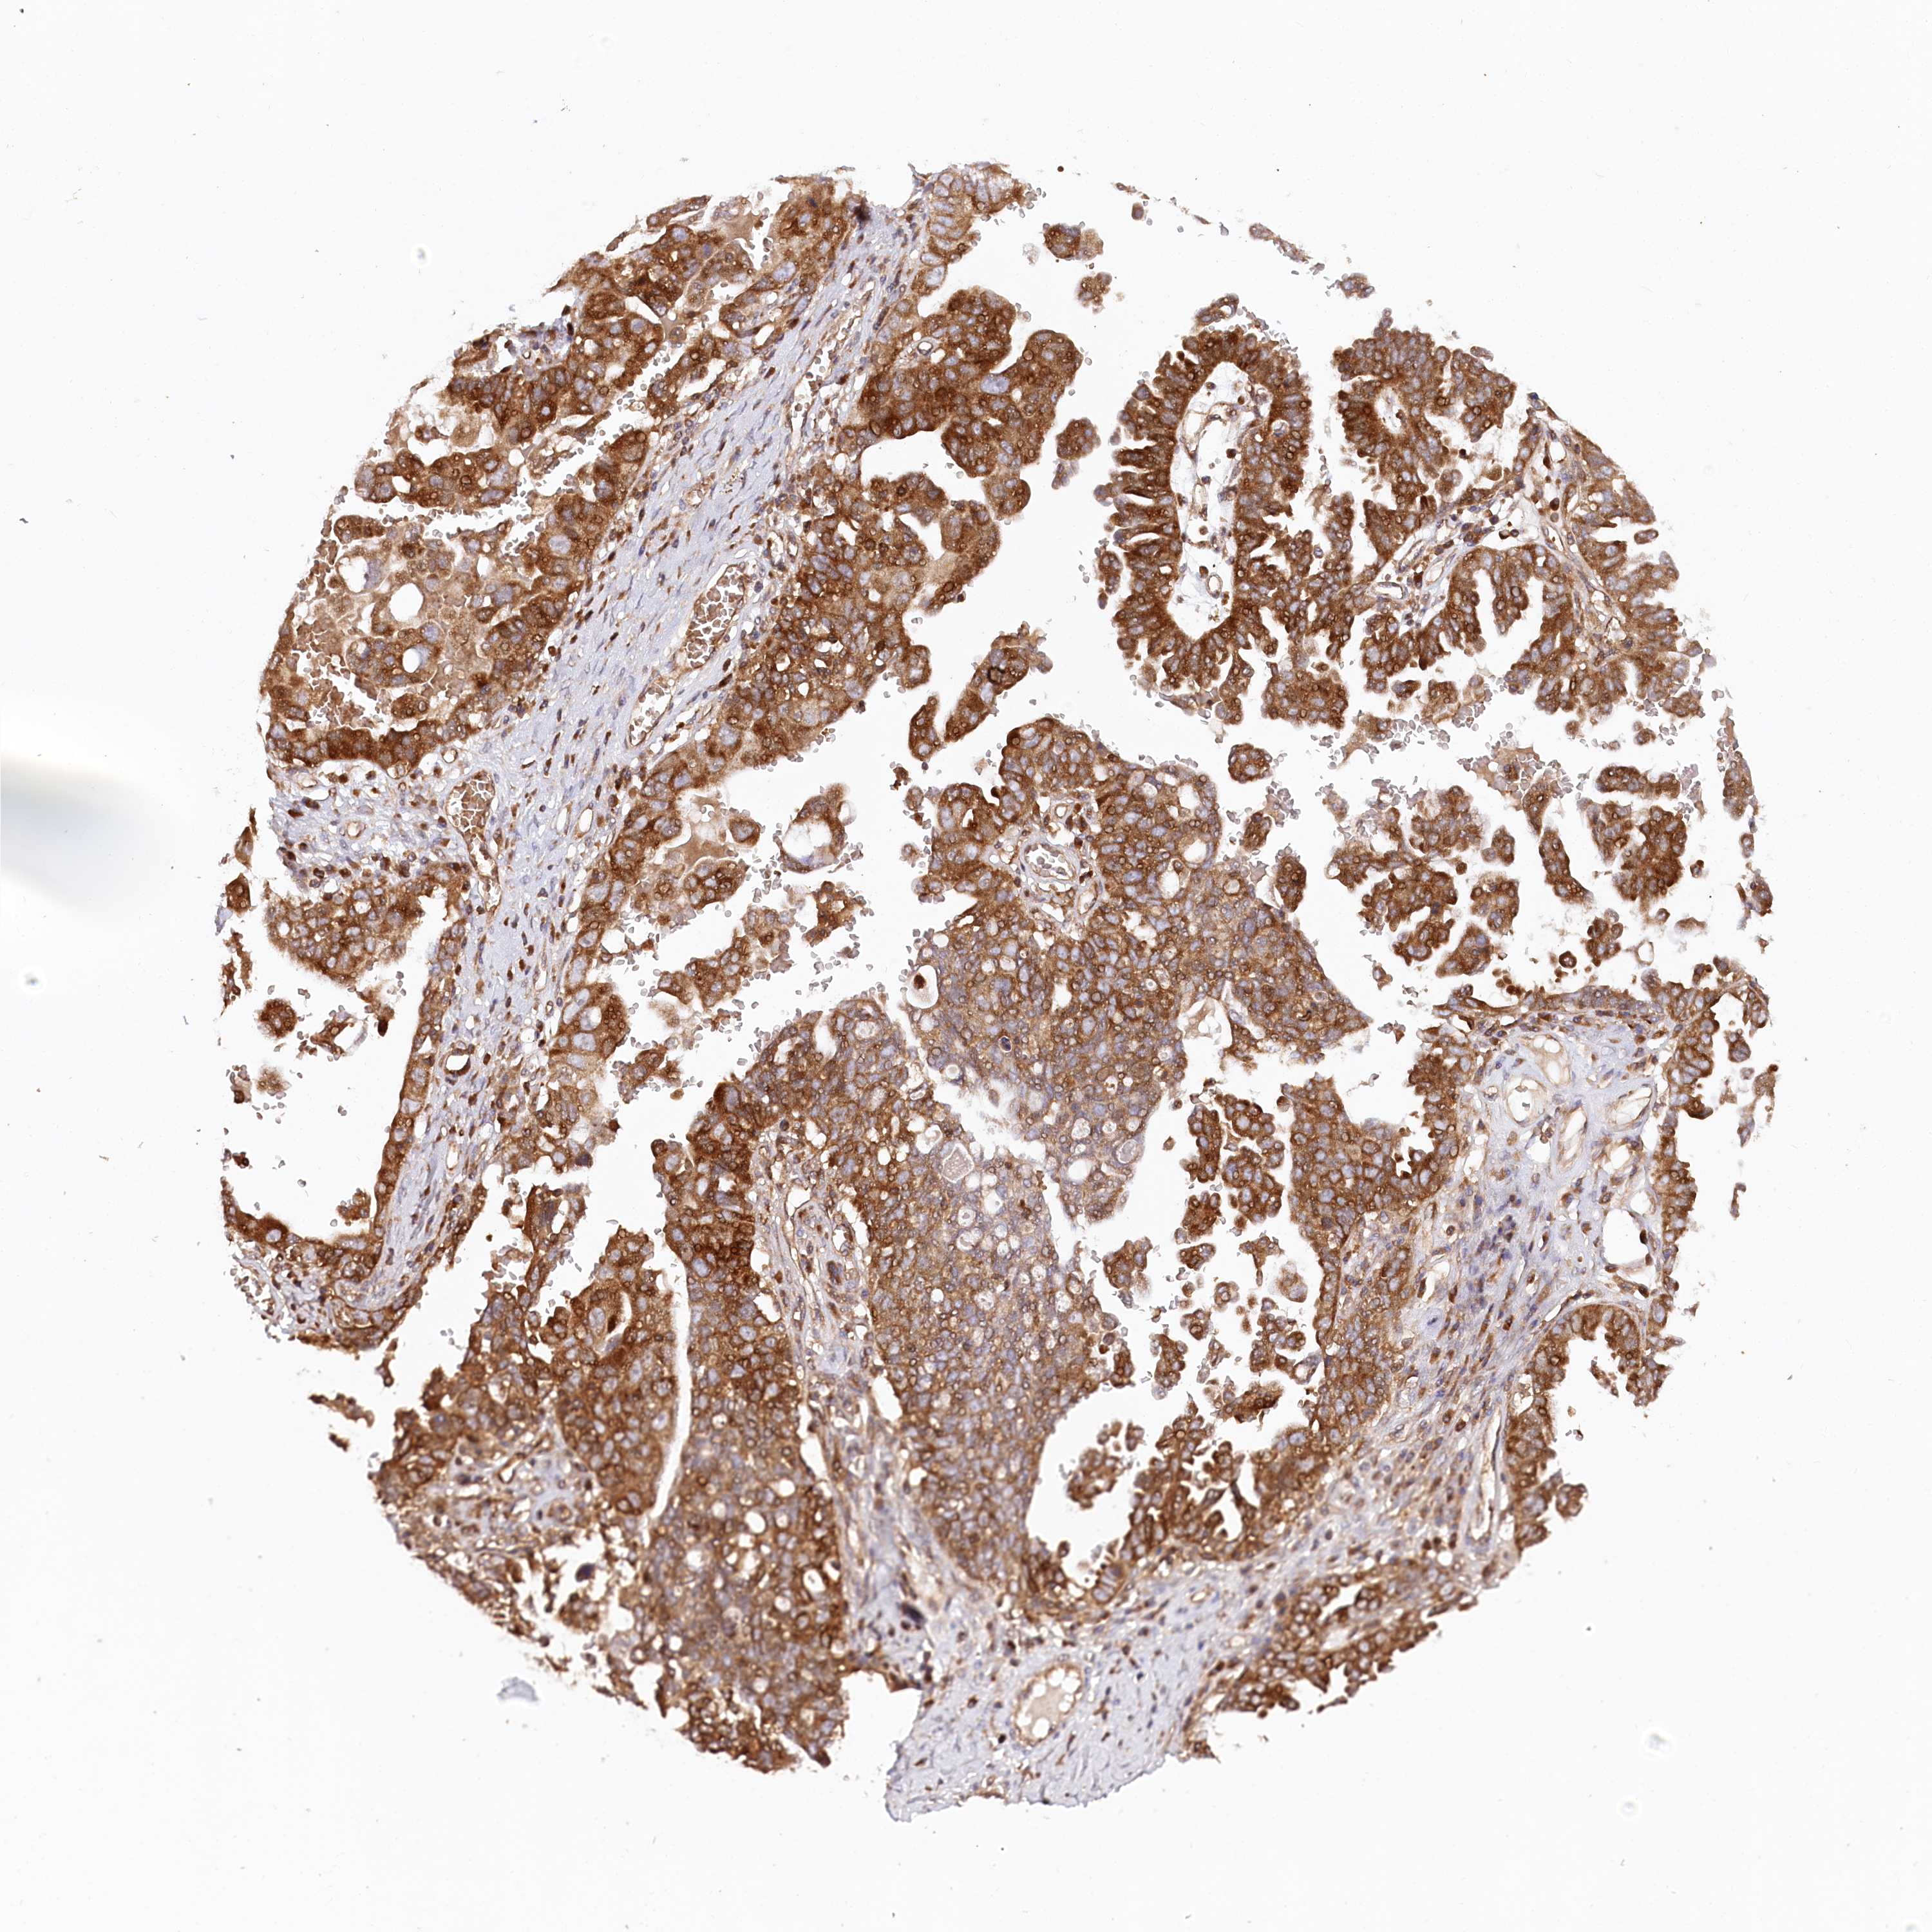

OVARIAN CANCER - Protein expressioni

A mouse-over function shows sample information and annotation data. Click on an image to view it in a full screen mode. Samples can be filtered based on level of antibody staining by selecting one or several of the following categories: high, medium, low and not detected. The assay and annotation is described here.

Note that samples used for immunohistochemistry by the Human Protein Atlas do not correspond to samples in the TCGA dataset.

Antibody stainingi

Antibody staining in the annotated cell types in the current human tissue is reported as not detected, low, medium, or high, based on conventional immunohistochemistry profiling in selected tissues. This score is based on the combination of the staining intensity and fraction of stained cells.

Each image is clickable and will lead to virtual microscopy that enables deeper exploration of all samples and also displays staining intensity scores, fraction scores and subcellular localization as well as patient and tissue information for each sample.

Antibody HPA035945

Antibody HPA056766

Antibody CAB037212

Cystadenocarcinoma, serous, NOS

Carcinoma, endometroid

Cystadenocarcinoma, mucinous, NOS

Carcinoma, NOS